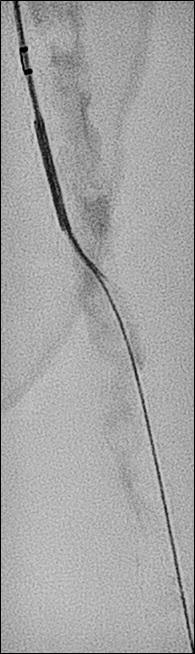

1. CTO of the left superficial femoral artery in a male patient suffering from severe claudication in the left calf

2. After subintimal passage, it was impossible to redirect the guidewire into the patent lumen distal to the CTO

3. Positioning of the BeBack catheter to re-enter the guidewire. Arrow indicates an orientation-marker

4. Marker appearing as a “C” indicates the direction of the needle, with the needle protruding maximally out of the BeBack catheter

5. An 0.018” guidewire passing into the patent distal lumen

6. Result after stenting